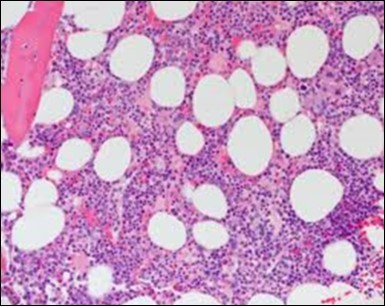

Figure 1.HCL: hairy cells infiltrating designated spaces(17).

Figure 2.HCL: hairy cells with projecting cytoplasm abutting bony trabaculae(18).

Figure 3.HCL: hairy cells dispersed within the native architecture(19).

Figure 4.HCL: hairy cells with widely spaced nuclei(20).

The classic hairy cell is medium sized with a magnitude of 10-14µm. The moderately abundant or variable cytoplasm may be transparent or mildly basophilic. The cellular surface with the characteristic serrated perimeter depicts innumerable fragile or stout extensions of cytoplasm ,particularly discernible on the phase contrast and electron microscopy. The cytoplasm may exhibit vacuoles with occasional azurophilic granules4. The nucleus may be elliptical or reniform, folded or indented with a coarse, reticulated or a finely dispersed chromatin and inconspicuous nucleoli along with infrequent mitosis. Bone marrow aspiration or bone marrow trephine biopsy may be inadequate for diagnosis in 30%-50% individuals4. The trephine sections of the bone marrow may depict a characteristic interstitial pattern of leukaemic infiltration. Generally the bone marrow is hyper-cellular, though it may be hypo-cellular in 10-15% individuals4. The leukaemia cell ingress may be diffuse or partial, although diffuse infiltration is frequent. The partial variety of leukaemic dissemination may be ineptly categorized with an indeterminate differentiation from the uninvolved marrow. The malignant insertions may initially emerge as miniature, undefined, cellular loci. The formalin fixed, paraffin embedded sections may elucidate a crystalline zone or a “halo” appearance of the cells with a circumscribed nucleus on account of the plentiful cytoplasm4. The cellular margins may be intertwined. Fixation of bone marrow smears with Zenker’s fixative may demonstrate a retracted cytoplasm of the hairy cells with a consequent disconnected structure. The bone marrow in the absence of a malignant process may be hypo-cellular or hyper-cellular. Reticulin stains may delineate an enhanced accrual of broad, dense reticulum fibres surrounding the aggregates of leukaemia cells with the fibrous circumlocution of individual malignant cell and fibrotic extensions into the abutting, uninvolved bone marrow4.

The leukaemia cells may enunciate a characteristic immune phenotype, crucial for a confirmatory diagnosis. The peripheral blood mononuclear B cell population may display a kappa or lambda light chain restriction. The phenotype of classic hairy cell leukaemia may be delineated by concurrent, immune reactive CD19+ CD20+,CD 11c+, CD25+, CD103+ and CD123+. An intensely immune reactive CD200+ and a non reactive CD27- antigen may be present2, 4. Evaluation of a trephine bone marrow biopsy and bone marrow aspirate may define the degree of tumour infiltration. A dry tap on account of prominent bone marrow fibrosis may be elucidated at preliminary diagnosis. A decline in the normal haematopoiesis may account for a hypo-cellular marrow in 10% instances. Gradation of cellular infiltrating of the leukaemia within the bone marrow may be appropriately investigated with immune –histochemical stains2, 4. Immune staining for CD20+, annexin 1 and VE1 (a BRAF V600E stain] may validate the diagnosis and precisely analyse the extent of malignant bone marrow infiltration[8]. Determination of BRAF V600E mutation may be critical in therapeutically non responsive individuals with applicable standard therapy or in instances of multitudinous reoccurrences[9]. Deploying inhibitors of BRAF V600E gene may be efficacious in patients impervious to approved therapy. The mutation necessitates a comprehensive scrutiny of the implicated individuals with a sensitive molecular assay which may discern up to < 10% of the hairy leukaemia cells appearing in the peripheral blood smears or bone marrow aspirates diluted with peripheral blood or aspirates elucidating a dry tap[2,4]. Allele specific polymerase chain reaction (PCR) or a next generation sequencing may be optimally employed to circumvent false negative outcomes. If the leukaemia cells are sparse or if particularly sensitive & efficacious molecular techniques are not accessible, the application of appropriate immune histochemical stains to the bone marrow biopsy such as a BRAF V600E mutation stain (VE1) may detect the hairy cells and conclusively diagnose the condition[2,4,10]. Figure 1, Figure 2, Figure 3, Figure 4, Figure 5, Figure 6, Figure 7, Figure 8, Figure 9, Figure 10, Figure 11, Figure 12, Figure 13, Figure 14.